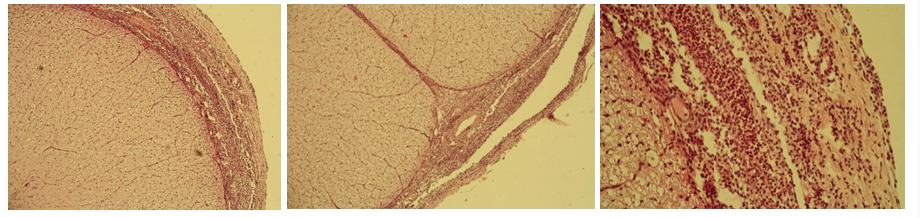

206. Meningitis spinalis purulenta

Description: Meninges (dura mater, arachnoidea, pia mater) are dilated and infiltrated by cells. Cell infiltrate consist of neutrophils. Tissue of the spinal cord is not seriously damaged. Dilated lymph and blood vessels, and purulent infiltrate. White areas represent some form of edematous reaction.

Etiology: Meningitis is caused by viral (non-purulent) and bacterial (purulent) infections. Purulent inflammation is most common in domestic animals, especially neonates.

Pathogenesis: Purulent meningitis is of hematogenous origin. The bacteria spread by blood and upon reaching the meninges, provoke an inflammatory response. Immune system reaction lead to accumulation of pus and inflammation of the spinal meninges, resulting in increased pressure of spinal cord and surrounding tissue.

159. Cysticercus ovis (brain)

Description: At the periphery, under the meninges, there is a cyst intruding into the brain. In the center there is necrosis, mostly infiltrated by eosinophils. Surrounding the necrosis is granulation tissue (with giant cells), which form a capsule of the host organism. Death of parasites probably results from the development of an immune reaction.

Etiology: Intermediate stage of Taenia ovis, a tapeworm of dogs. Found in sheep after ingestion of eggs from contaminated food or water.

Pathogenesis: Eggs hatch in the intestine and migrate through the bloodstream to various tissues in the body, including the brain. There, the larvae form a cyst (cysticercus) and form a condition known as cerebral cysticercosis